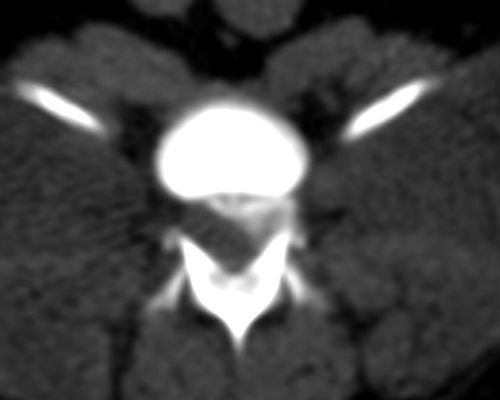

TC MULTISTRATO